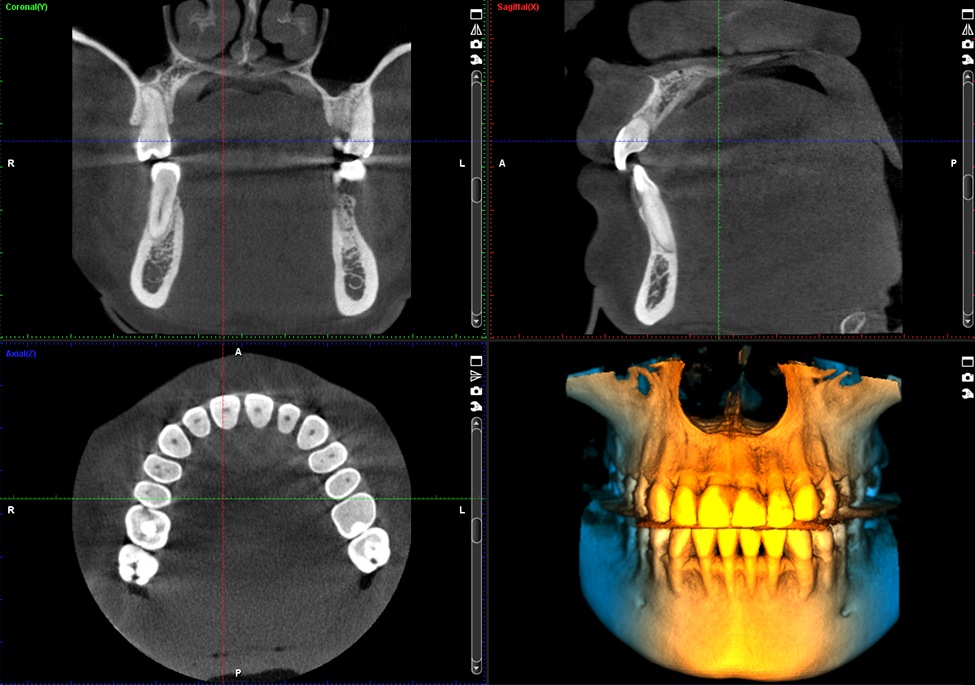

CBCT (Cone Beam Computed Tomography) is the latest , advanced and state of the art imaging approach that uses a cone-shaped X-Ray beam to create detailed 3D images of your teeth, jaws, and surrounding structures.

Unlike traditional methods like X-Rays, CBCT scans provide more accurate and comprehensive data, making them invaluable for dental diagnostics and treatment options. Essential features of a Dental CBCT scan include:

- High-resolution 3D imaging.

- Close visualization of bone structures, nerves, and soft tissues.

- Reduced exposure to radiation compared to conventional CT scans.